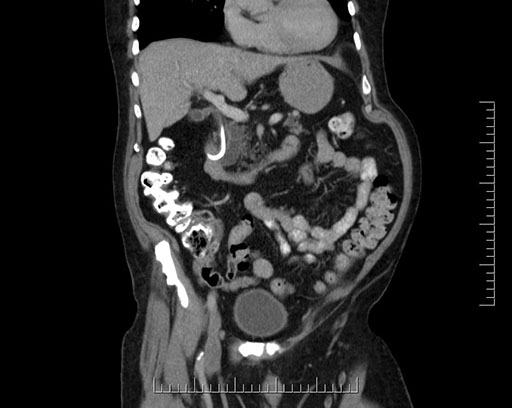

Coronal - stented